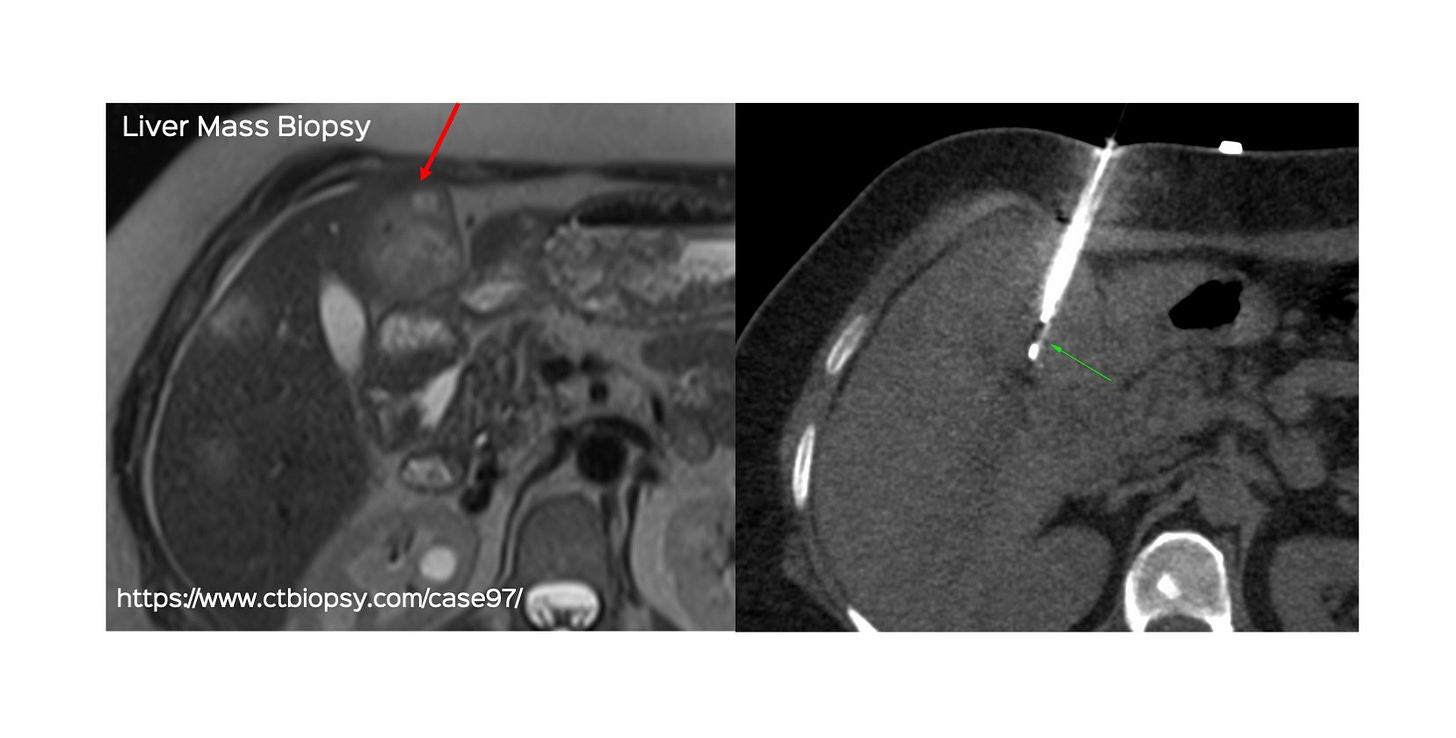

https://www.ctbiopsy.com/case97/